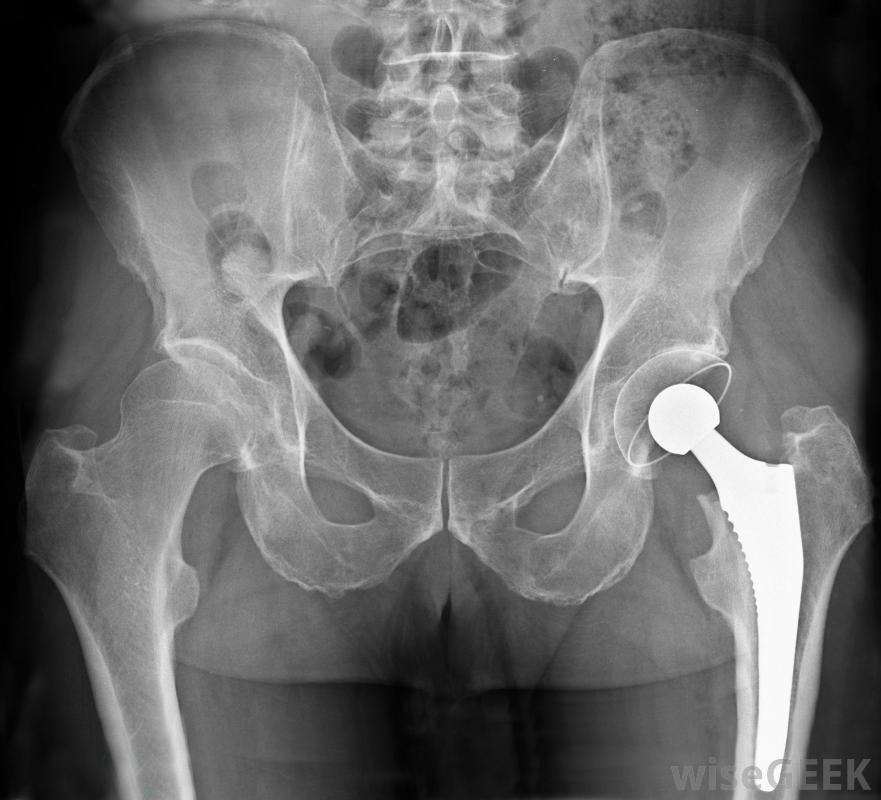

骨科医生可能专门从事髋关节置换或其他外科手术。骨科医生可能对整个肢体有全面的兴趣。例如,专家只能进行腿部手术,但会对腿部进行任何骨骼、关节或肌肉手术。医生可能会发现自己正在修复复合骨折,即骨折穿过皮肤,然后处理髋关节脱位的病例。同样,一些骨科医生治疗整个手臂的疾病,从肩关节到手指

一些骨科专家将专攻体育,从与高中运动员合作开始然而,更常见的是骨科专科医生对手臂和腿部的关注范围较窄最常见的腿部整形外科专业分为膝盖和臀部以及脚和脚踝。对于手臂,医生通常集中在手和手腕或肩和肘关节上。骨科医生只需进行关节置换,就可以在一个部位进行更有限的治疗。例如,专门研究膝关节和髋关节的矫形外科医师将替换这些关节,但拒绝接受髋关节或膝关节周围肌肉撕裂的患者。